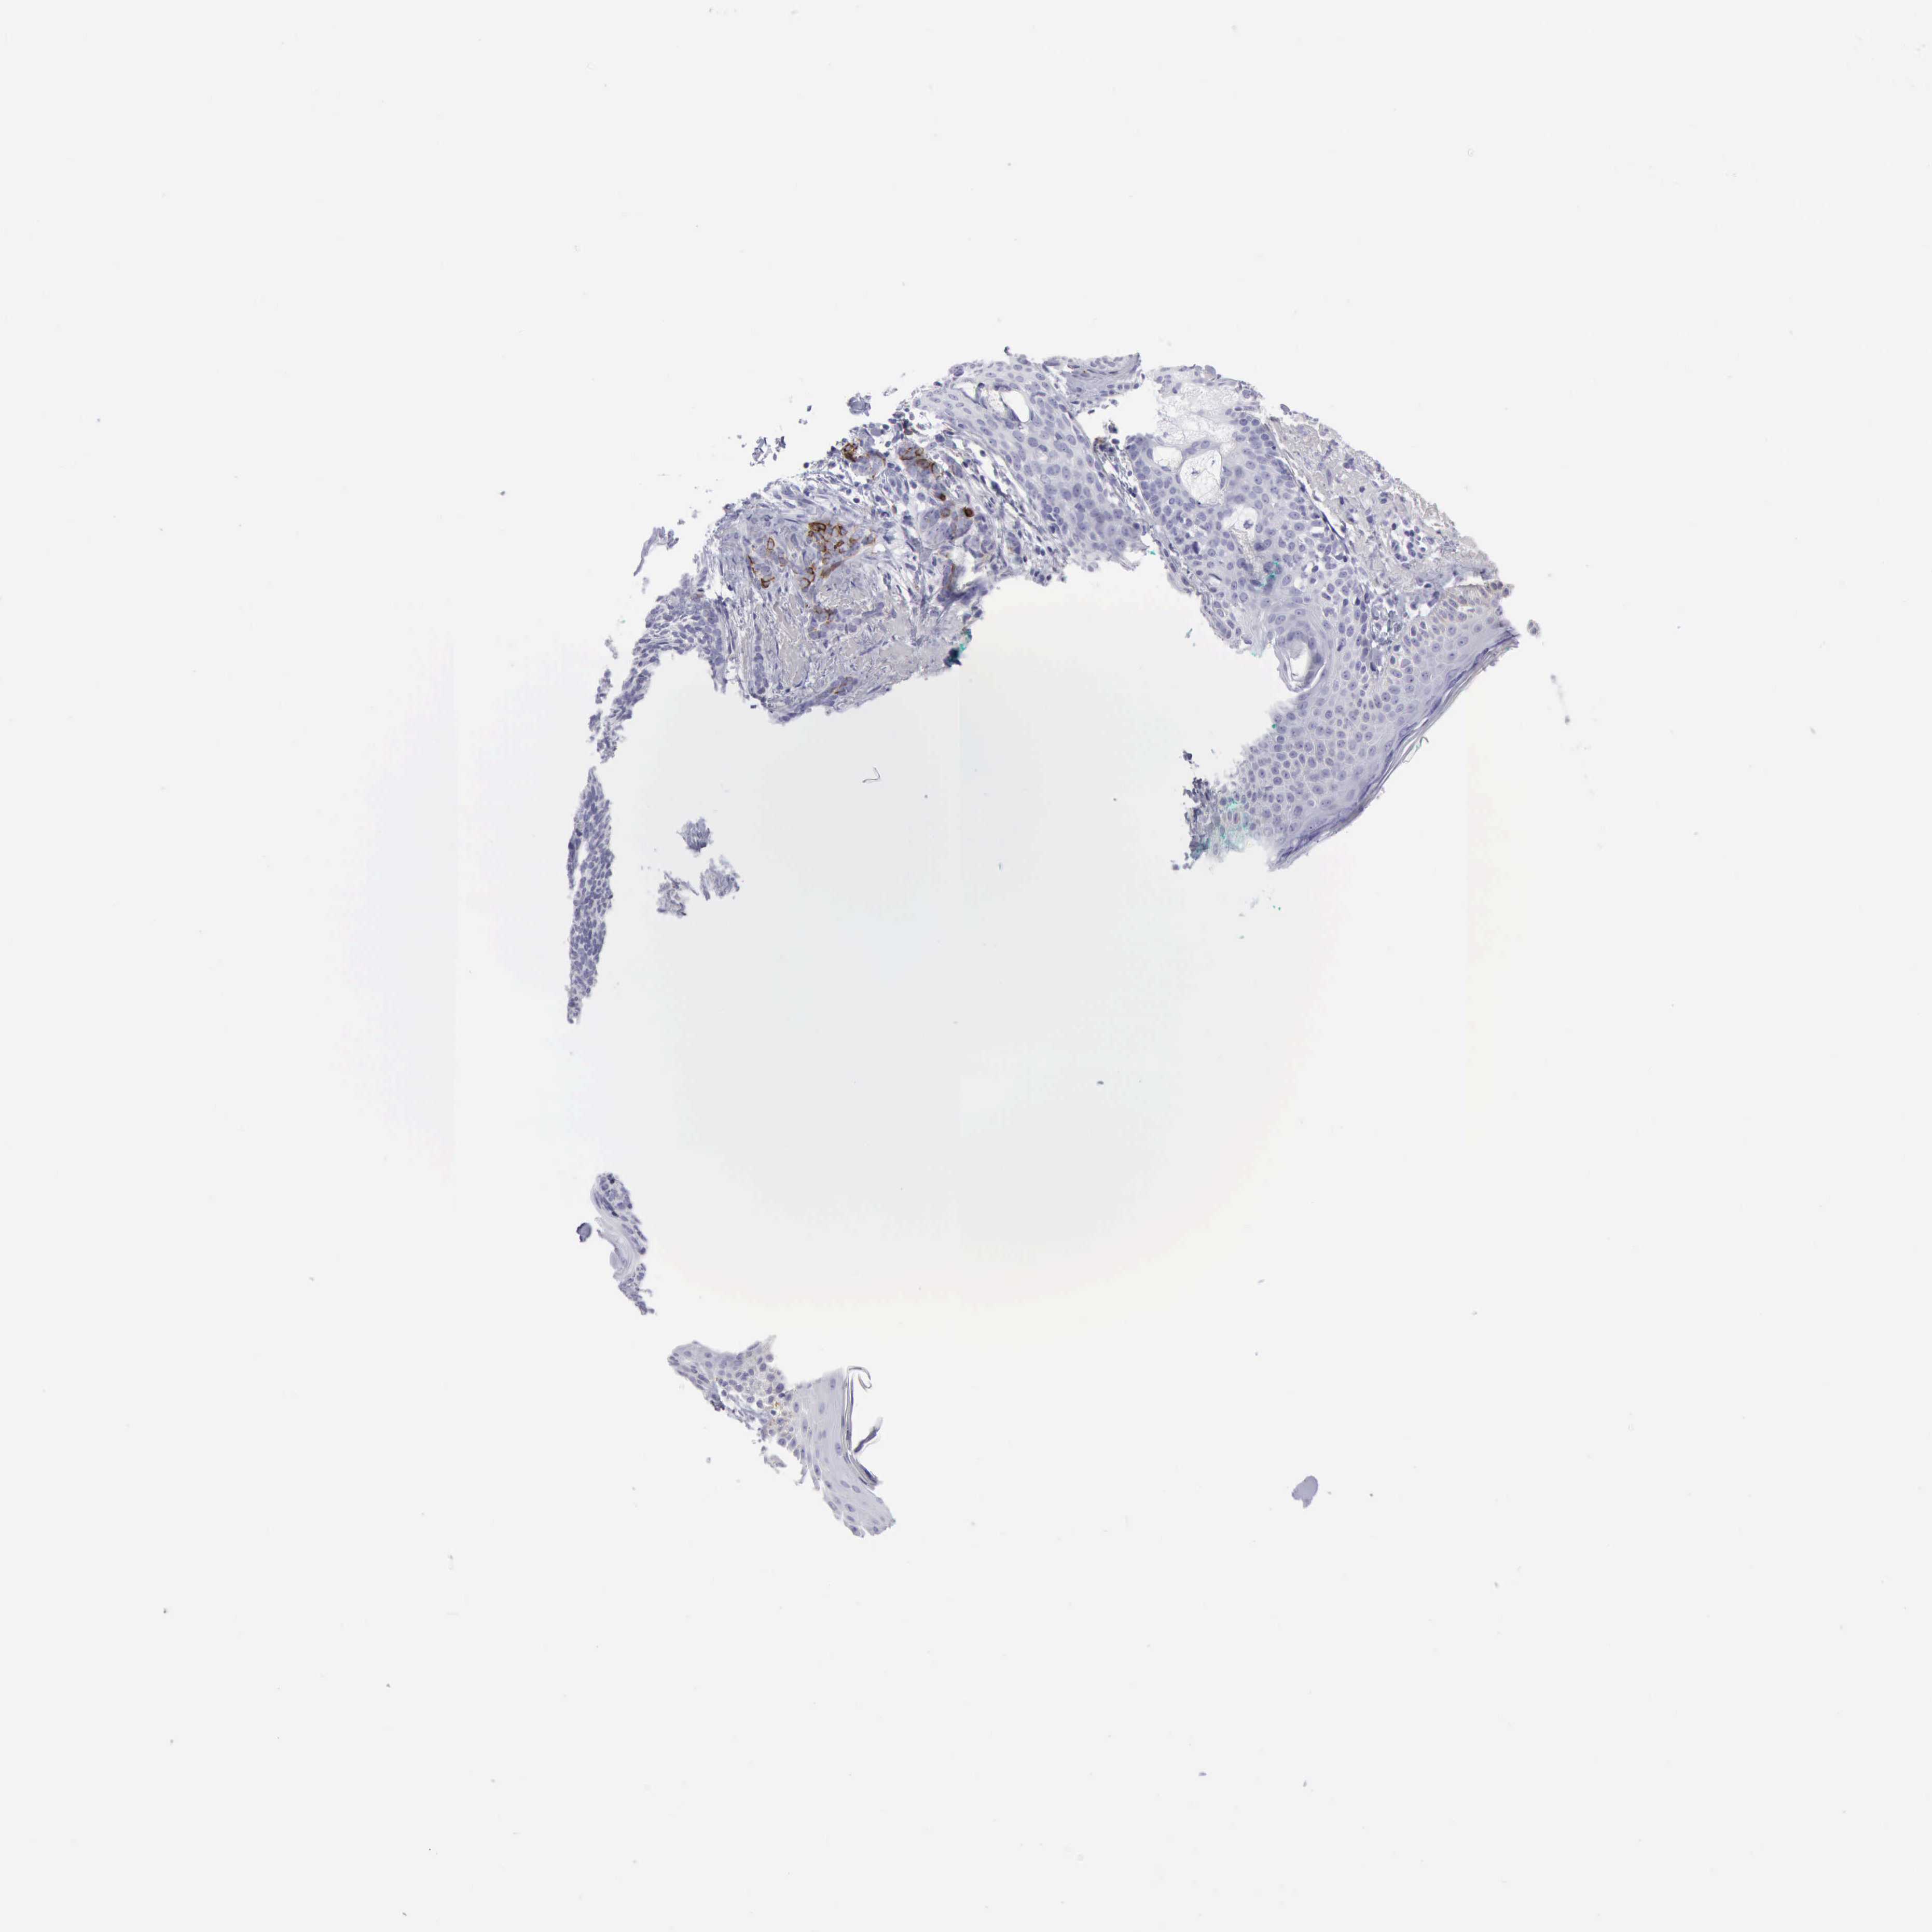

SKIN CANCER - Protein expressioni

A mouse-over function shows sample information and annotation data. Click on an image to view it in a full screen mode. Samples can be filtered based on level of antibody staining by selecting one or several of the following categories: high, medium, low and not detected. The assay and annotation is described here.

Each image is clickable and will lead to virtual microscopy that enables deeper exploration of all samples and also displays staining intensity scores, fraction scores and subcellular localization as well as patient and tissue information for each sample.

Antibody CAB000142

Basal cell carcinoma

Squamous cell carcinoma, NOS

Squamous cell carcinoma, metastatic, NOS

Squamous cell carcinoma in situ, NOS

Adnexal tumor, benign